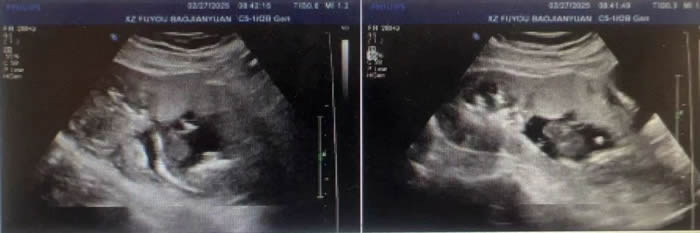

胎盤植入和(hé)前(qián)置胎盤是妊娠期極為凶險的並發症,尤其對經曆過多次剖宮(gōng)產的產婦來說(shuō),風險更是(shì)倍增。近(jìn)日,徐州市婦幼保健院成功救治一名高(gāo)危孕產婦,經曆4次剖宮產後,再次懷(huái)孕卻在孕13周被診斷為胎盤植入、胎盤前置狀態,隨時麵(miàn)臨大出血風險。

“胎盤植入會導致胎盤與子宮肌層異常粘連,甚至穿透子宮(gōng)壁,而前置胎盤則意味著胎盤覆蓋宮頸(jǐng)內口,分娩時極易引發大出血,危及母嬰(yīng)生命。”婦女保健(jiàn)部部長梁麗主任如是說,“這位產婦的情況極為複雜,她的子宮內膜因多次手術受(shòu)損,胎盤植入風險極高(gāo)。一旦進入分娩期,可(kě)能會在短時間內大量出(chū)血(xuè),甚至(zhì)需要切(qiē)除子宮保命。”

前置胎盤是(shì)指妊娠28周後胎盤附著於(yú)子(zǐ)宮下段,胎盤下緣達到或覆蓋宮頸內口。由於前置胎盤附著於缺少肌(jī)纖維的子(zǐ)宮下(xià)段,如(rú)果有剖(pōu)宮產手術史或(huò)合並子宮內(nèi)膜損傷,可增加並發胎盤植入的風險。

凶險性前置胎盤,指前次有剖宮產史,此(cǐ)次妊娠為前置(zhì)胎盤。剖宮產術後再次(cì)妊娠的胎盤附著於子宮瘢痕上,使發生穿透性胎盤植入的風險明顯增加,是前(qián)置胎盤中最嚴重的類型,需要進行早期識別(bié)。

胎(tāi)盤植入:凶險性前置胎盤常合並(bìng)胎盤植入,即胎盤侵入或者穿透子宮壁生長,甚至長(zhǎng)到子宮周圍的膀(bǎng)胱、直腸等器官,在胎兒娩出後,胎盤不能自行剝離。凶險性前置(zhì)胎盤合並胎盤植入可導致孕產婦發生嚴重的產科出血,彌漫性血管內凝血,休克,甚至發(fā)生子(zǐ)宮切除,感染(rǎn)及死亡等嚴(yán)重並發症,是目(mù)前國內外孕產婦(fù)死亡的(de)主要原因。